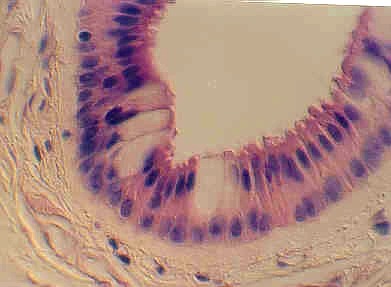

In the interlobar connective tissue, large EXCRETORY DUCTS can be seen. These are distinguished by their layers of nuclei and Goblet cells. The following photographs show views of this type of duct. Identify the Goblet cells.

Excretory ducts can also be found in the submandibular gland. They are distinguished by the the yellow staining Goblet cells. Higher magnification showing Goblet cells in the EXCRETORY DUCT of the Submandibular gland. What is the difference between intercalated ducts and striated ducts?

Classify the epithelium in the EXCRETORY DUCTS. Look at the lumenal cells for the proper “shape classification”.